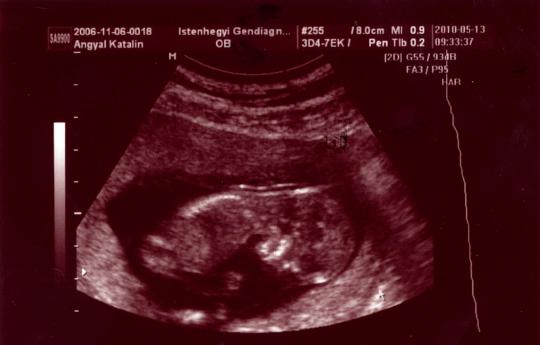

Angie, nagyon örülök, hogy mindenk okés volt tegnap HK-nál! most már fellélegezhetsz, szerencsére minden okés a kisbabáddal!